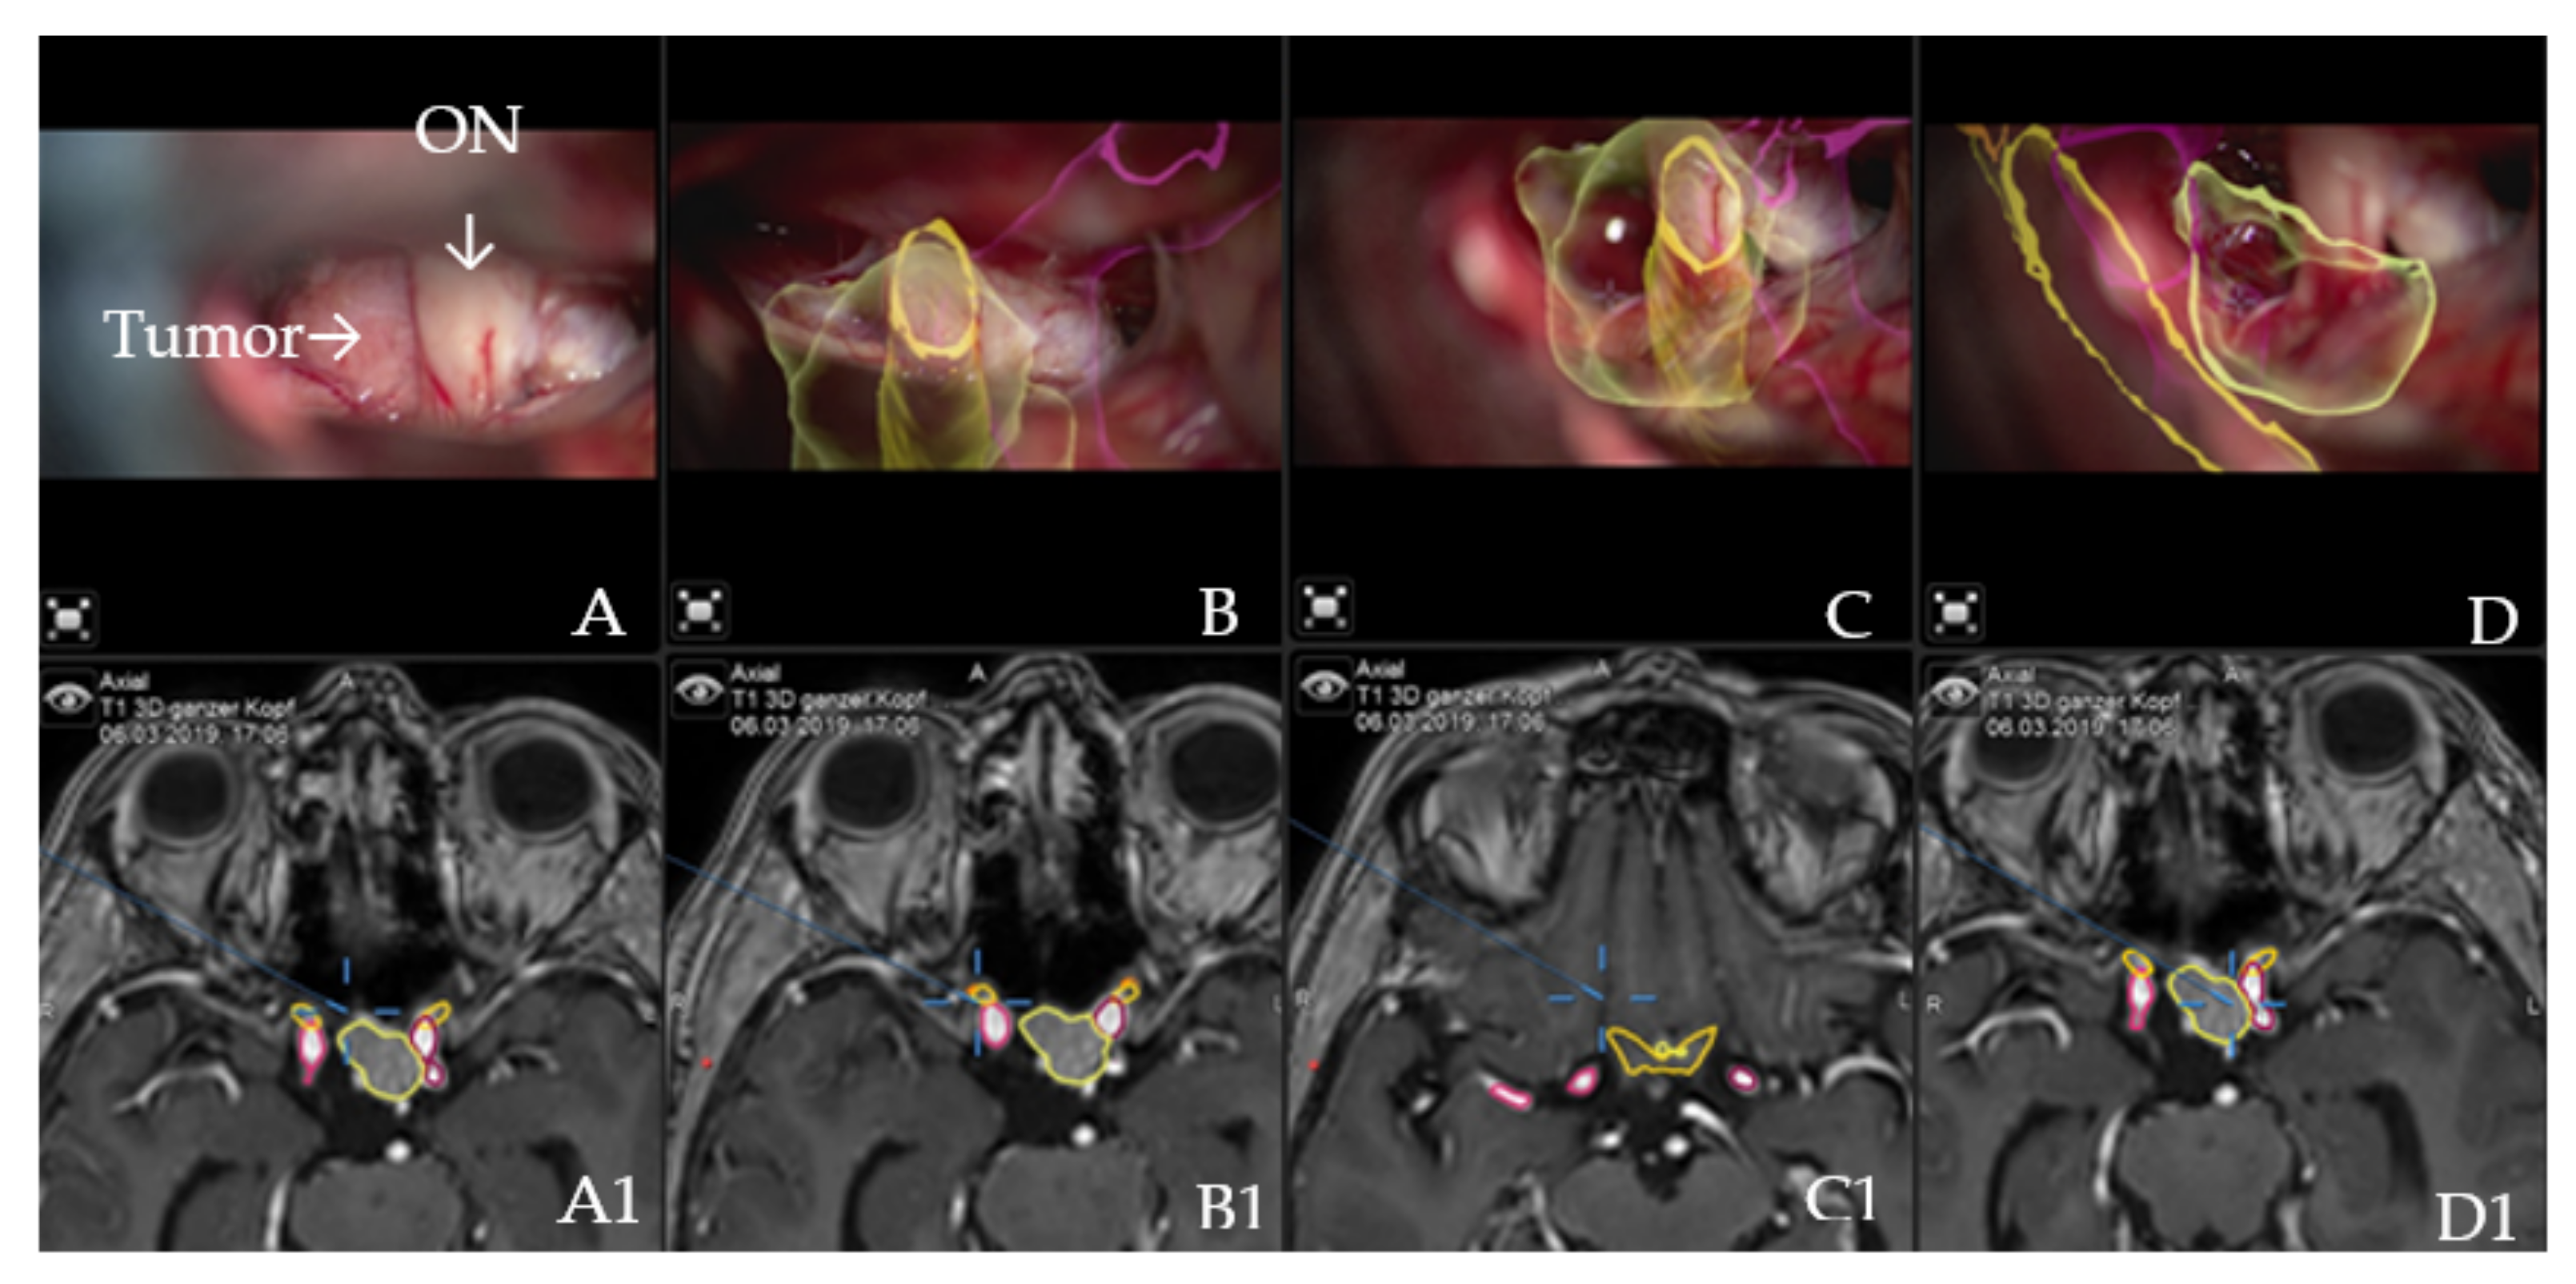

Illustrative Cases